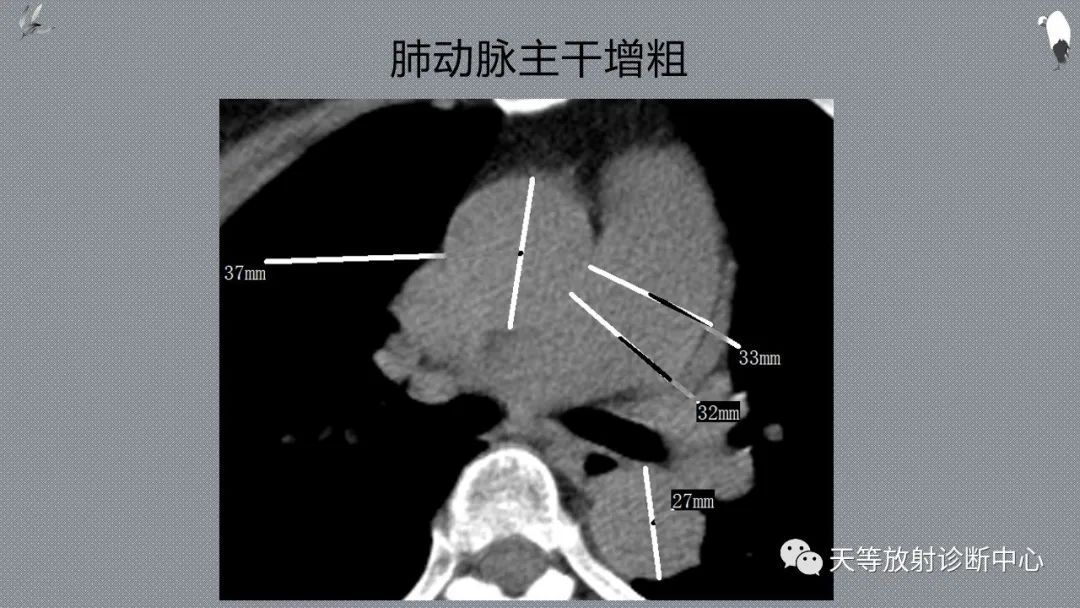

应该注意以下鉴别:全小叶肺气肿、肺动脉高压、哮喘的鉴别